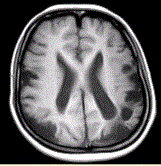

问题 女性,22岁。癫痫发作及智力异常。MRI显示见下图。 有关该病的描述,正确的是

选项 A.多种原因引起颅底大动脉严重狭窄或闭锁,并可见脑底部代偿性异常血管网 B.MRT2WI显示基底节区多发点状血管流空信号 C.DSA显示willis环闭塞,颅底区烟雾状侧支循环 D.CT显示低密度病灶,为缺血、梗死所致,特征是双侧性和多发性 E.影像学首选MRA及MRI F.主要发生在老年人 G.多见于颈内动脉床突上段和大脑前、中动脉近段和基底动脉远端

答案 ABCDEG